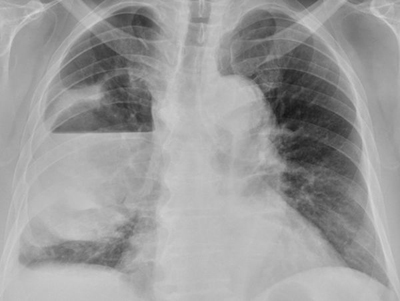

68歲的張先生為高血壓患者,平時有抽菸和喝酒習慣,突然出現咳嗽和發燒症狀,時間長達兩周,在診所拿藥服用後仍未改善。最後除了發燒和咳嗽加劇外,還合併右側胸痛及呼吸漸喘等症狀,才至醫院治療。台南市立醫院胸腔暨食道外科醫師方副吉表示,患者出現14公分大的肺膿瘍,因此緊急以廣泛性抗生素治療,狀況才開始好轉。

肺膿瘍是一種肺實質化膿性的細菌感染,會造成組織壞死,引發肺實質開洞而形成空氣液面變化。方副吉說,為治療患者的右側肺膿瘍,安排電腦斷層,經皮胸腔導管引流出約700 cc帶有惡臭味的黃白色膿液後,再治療呼吸喘的症狀,患者病情才進一步改善。至於患者的膿液,培養的結果是厭氧性細菌,必須使用抗生素治療至少四周以上。雖然感染狀況沒擴散,但仍面臨隨時要以手術介入可能。